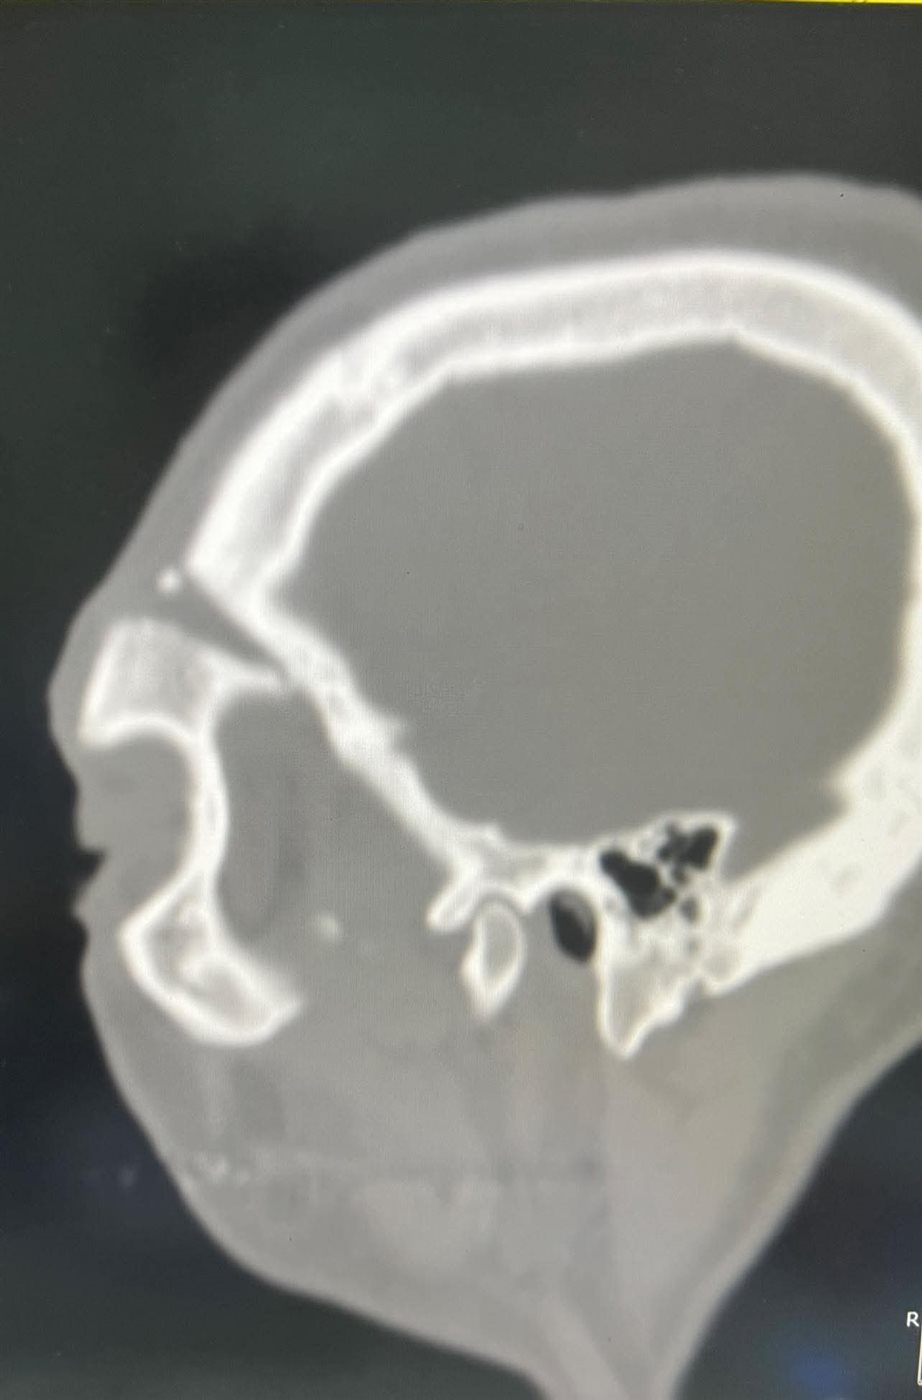

وكان المريض قد وصل إلى المستشفى بعد مرور 40 يومًا على الحادث، حيث كان قد مكث بإحدى المستشفيات دون تدخل جراحي نظرًا لصعوبة الحالة، ما أدى إلى بدء التحام العظام بشكل غير صحيح، وزيادة تعقيد التدخل الجراحي.

وخلال عملية استمرت نحو 9 ساعات متواصلة، تم تنفيذ تدخل جراحي متكامل شمل استخدام مدخل جراحي تجميلي (Bicoronal Approach) لإتاحة رؤية جراحية واسعة مع الحفاظ على الشكل الجمالي، إلى جانب التعامل مع قاعدة الجمجمة وإجراء Cranization للجيب الجبهي، بما يضمن حماية المخ.

كما تم إعادة بناء محجر العين والجيب الأنفي باستخدام عظام ذاتية من المريض (Autogenous Bone Graft) مع تدعيمها بشبكة تيتانيوم، إلى جانب إعادة تثبيت عظام الوجه والجمجمة باستخدام الشرائح والمسامير لاستعادة التماثل التشريحي الكامل.